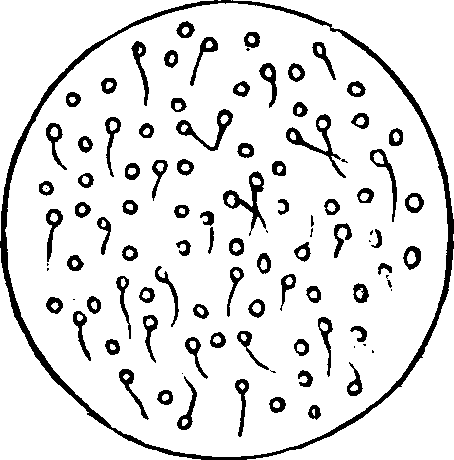

Generation. So long as the vital principle remains in the sperm-cell, it lies dormant. That part of the cell which contains this principle is called the spermatozoön, which consists of a flattened body, having a long appendage tapering to the finest point. If it be remembered that a line is the one-twelfth part of an inch in length, some idea may be formed of the extreme minuteness of the body of a human spermatozoön, when we state that it is from 1/800 to 1/600 part of a line, and the filiform tail 1/50 of a line, in length. This life-atom, which can be discerned only with a powerful magnifying glass, is perfectly transparent, and moves about by executing a vibratile motion with its long appendage. Within this speck of matter are hidden the multifarious forces which, under certain favorable conditions, result in organization. Magnify this infinitesimal atom a thousand times, and no congeries of formative powers is perceived wherewith to work out the wonders of its existence. Yet it contains the principle, which is the contribution on the part of the male toward the generation of a new being.

Fig. 1. A. Human

Spermatozoön magnified about 3,800 diameters. B. Vertical and

lateral views of spermatozoa of man. C, D, E, F. Development of

spermatozoa within the vesicles of evolution. G. Cell of the sponge

resembling a spermatozoön. H. Vesicles of evolution from the

seminal fluid of the dog in the parent cell I. Single vesicles of

different sizes. J. Human spermatozoön forming in its cell.

K. Rupture of the cell and escape of the spermatozoön.